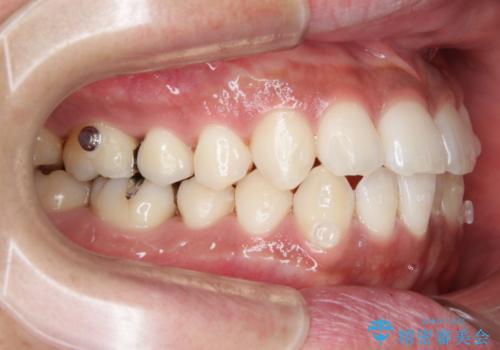

- 上下の前歯のがたつきが気になるとご相談にいらした方です。光加速矯正装置(オルソパルス)を用いて短期間で仕上げることが出来ました。

一般的に噛む力が強い方は矯正治療に時間がかかると言われてます。光加速矯正装置(オルソパルス)を用いることで短期間で仕上げることができました。